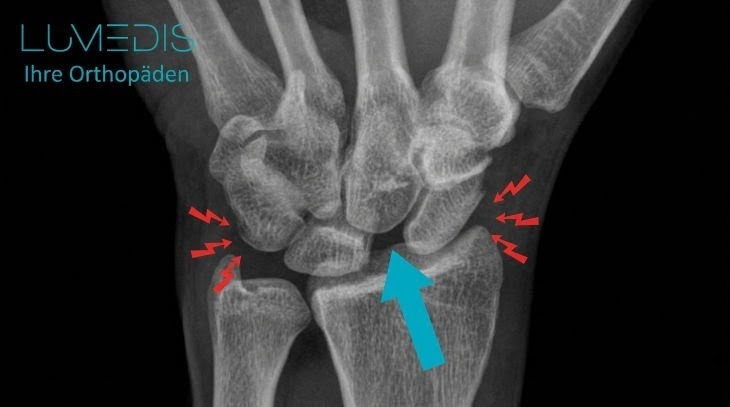

Röntgen einer SLD (scapholunären Dissoziation) linkes Handgelenk

Röntgenbild einer scapholunäre Dissoziation (SLD)

Der türkise Pfeil zeigt auf die zu weit auseinander stehenden Handwurzelknochen von Kahnbein und Mondbein.